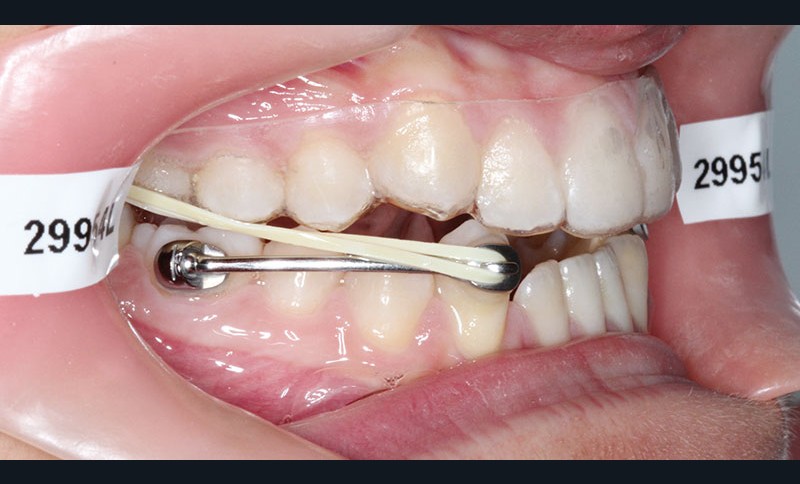

1re phase : recul des secteurs latéraux mandibulaires avec le Motion Classe III Carriere (fig. 4 à 6)

Nous mettons en place des bras latéraux Motion associés à des élastiques intermaxillaires ancrés sur des brackets sur 17 et 27 et une gouttière thermoformée maxillaire portée jour et nuit :

• 1er mois : élastiques 6 oz. 1/4”

• 2e mois et suivants : élastiques 6 oz.1/4“

L’objectif de cette étape est d’obtenir un recul des secteurs latéraux mandibulaires afin de positionner les molaires et canines en classe I et de réorienter le plan d’occlusion en haut en avant.